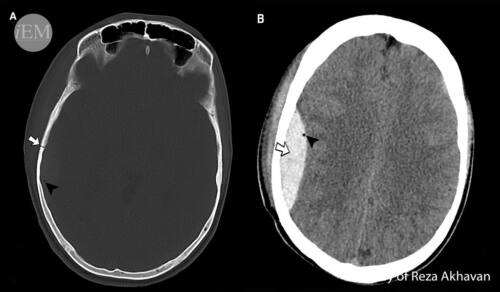

Диагнозата на епидурален хематом се потвърждава от невроизобразяващите методи на основно изследване – компютърната томография, наричана за кратко -КТ. По характера на плътността се получава и информация за давността на хематома. Острите хематоми са по-тъмни, поради плътността на кръвните съсиреци, докато хроничните се виждат бледи, тъй като кръвта при тях е втечена и лизирана кръв. Но не е изключено те да бъдат и със

смесена или дори с нормална плътност, еднаква на мозъчната, при което да се налага изследването да се извърши и с венозно приложение на контрастна материя.